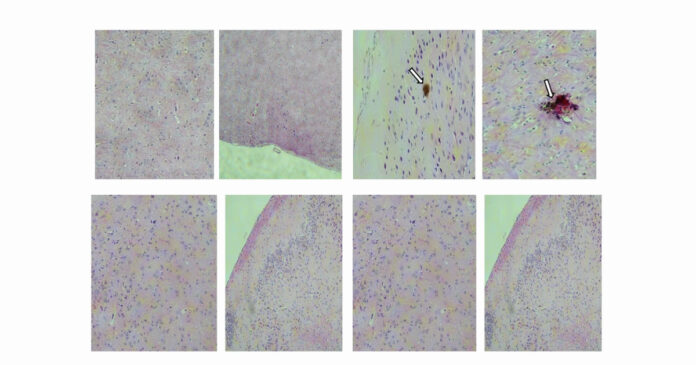

Os testes realizados em camundongos geneticamente modificados e mais suscetíveis ao vírus mostraram que a vacina induziu a produção de anticorpos que neutralizaram o vírus, não permitiu a exacerbação da infecção e, por consequência, o surgimento de sintomas.

Os pesquisadores também investigaram os efeitos da infecção pelo vírus zika em diversos órgãos de camundongos – como cérebro, rins, fígado, ovários e testículos. “A vacina demonstrou capacidade de proteger camundongos machos contra danos testiculares”, diz Côrtes. “Isso é importante diante dos riscos conhecidos da transmissão sexual do vírus zika e de seu potencial para causar lesões nos testículos, o que pode afetar negativamente a espermatogênese e a saúde reprodutiva como um todo”, ressalta o pesquisador.